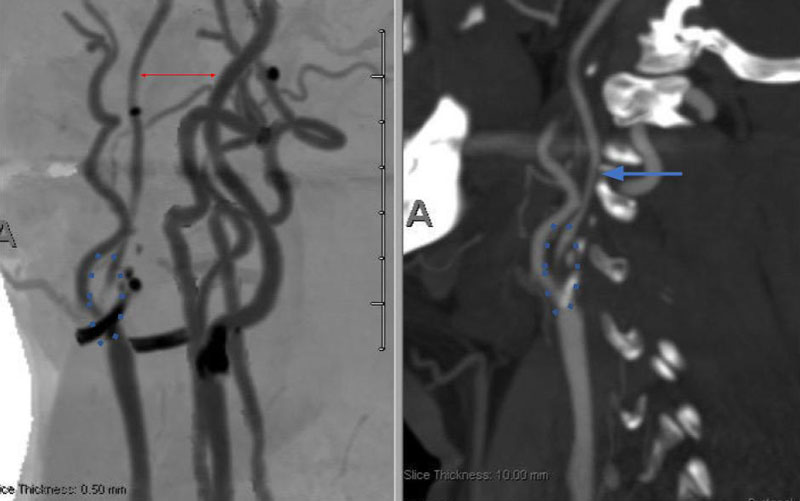

Under Monitored Anesthesia Care, and systemic anticoagulation (ACT maintained above 250), a 6 French Guide Sheath was positioned within the distal cervical right Common Carotid Artery (CCA). Slow antegrade filling of the right internal carotid, MCA, and ACA was observed compatible with flow limitation, as well as physiologic need for this relatively isolated circulation. In addition, primary embolic protection filter placement was not considered technically feasible secondary to the severity of the “string” like stenosis. Serial primary angioplasty with 2 x 20 mm and a 2.5 x 20 mm balloon was gently performed to 10-12 ATM, creating an improved channel within the stenosis. An exchange length .014 (300 cm) “buddy” wire was then positioned across the lesion to maintain access, as an embolic protection filter was carefully navigated and deployed in the distal cervical ICA. Subsequently, a 4 x 40 mm PTA balloon was then utilized to perform angioplasty with embolic protection, followed by placement of a 40 mm stent tapering from 6 to 8 mm from distal to proximal within the right ICA and CCA. Post Stenting angiography demonstrates no significant residual stenosis with significantly enhanced right hemispheric perfusion on angiography (Figure 5).

Figure 5. A) Pre-Dilatation with 2.5 x 20mm balloon (arrow) ; B) Initial PTA result with “Buddy Wire”; C) final Post PTA and Stent with no significant residual stenosis across the entire length of the atherosclerotic segment (dotted).